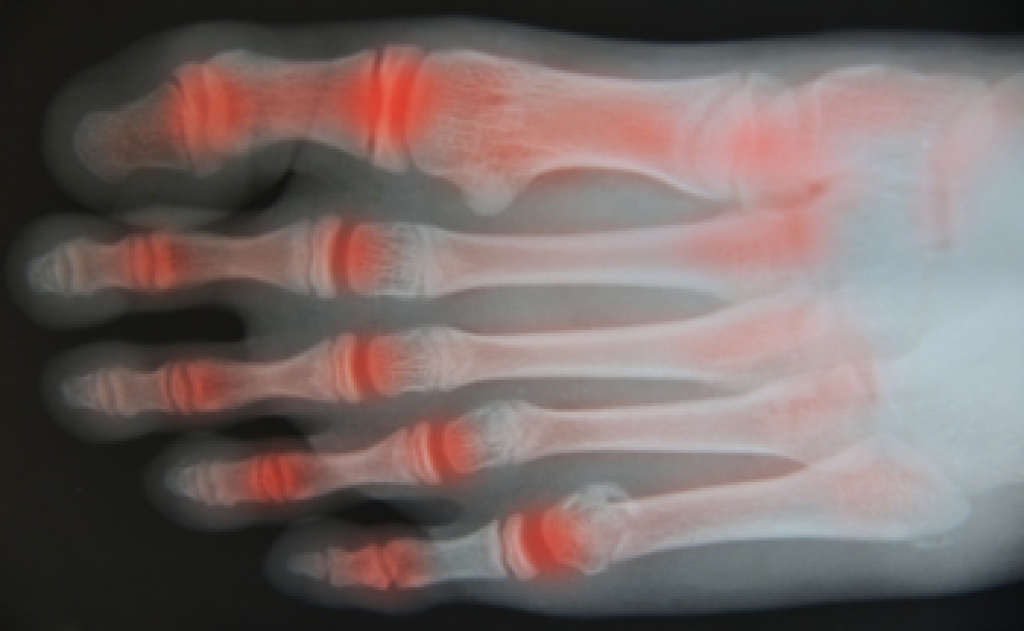

- Severe arthritis that has caused bone issues